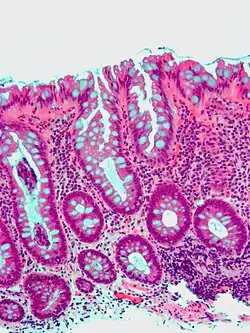

Colorectal adenocarcinoma 100%

• In carcinoma in situ (Tis): cancer cells invading into the lamina propria, and may involve but not penetrate the muscularis mucosae. Can be classified as "high-grade dysplasia", because prognosis and management are essentially the same.[10]

• Invasive adenocarcinoma: Extending through the muscularis mucosae into the submucosa and beyond.[10]